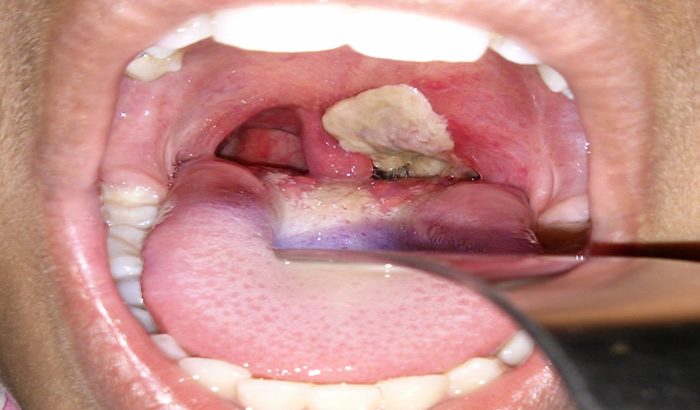

The symptoms of diphtheria in children can often mimic those of common respiratory infections. Initially, a sore throat, mild fever, and swollen lymph nodes may appear. However, as the infection progresses, a thick, grayish membrane forms in the throat, making it difficult to breathe. This can lead to severe respiratory distress and may require urgent medical intervention. Hoarseness, coughing, and difficulty swallowing are also common signs. In advanced stages, complications may include heart problems and nerve damage.